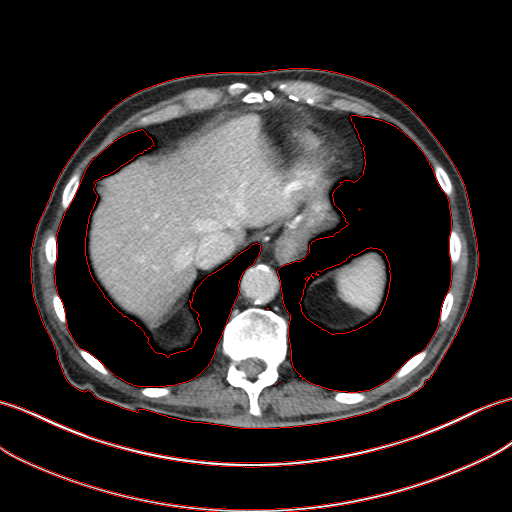

As shown in Table 3, DIP has exhibited the worst performance among all the methods. On the other hand, the ConsensusNet yielded a better FID and TML than BM3D but a lower PSNR and SSIM than other methods. The ConsensusNet divided the original projection data of the low dose CT image into two subgroups and back-projected to create the noisy input signal. Consequently, the noisy input image is much noisier than the original LDCT image. Also, the structural loss occurred during the generation of noisy images, so as a result, the PSNR and SSIM of this method are lower than other methods. Texture matching loss (TML) is used to measure the texture difference between the reconstructed and original images. The lower value of TML indicates that the generated texture is similar to the original. In comparison, FID estimates the distance between the distribution of the generated image and real images. A lower value of FID signifies the generated images are more similar to the original image. The current deep learning era demands a denoised image with a low value of these metrics. These denoised images may be used as input for other image classification tasks or segmentation networks. In this regard, the ConsensusNet is superior to the BM3D because it uses the deep neural network’s expression power. CycleGAN is another powerful unsupervised method for image-to-image translation; it achieved better performance than the other methods. However, CycleGAN has a lot of bottlenecks, e.g., longer training time, computation power, hyper-parameter tuning, etc. All these bottlenecks make CycleGAN ill-suited for practical deployment. Meanwhile, our proposed method has achieved the highest PSNR, SSIM, FID, and VIF among all the other methods. Next, we compare the result of denoising visually in Figure 6. It can be observed that the proposed method performs significantly better than the other unsupervised methods. BM3D output produced a blurry denoised image and contained many splotchy artifacts. The same blurriness can be observed in the output of ConsensusNet, and DIP, although noise suppression is adequate, and splotchy artifact is absent. In the output of CycleGAN, we can observe the presence of residual noise, especially in the high noise regions. Next, we identified one low attenuated lesion in the sample image and marked the lesion with a red colour bounding box. The zoomed view of the region inside the bounding box is given in Figure 7. In our method’s output image, the lesion’s visibility is enhanced significantly than in other methods. Despite being an unsupervised method, the visibility of the lesion is comparable with the original NDCT image. Also, from the zoomed view, we can perceive that our method has suppressed the granular pattern without losing the original image’s texture.

Figure 6: Result of denoising for comparison. We have shown an example of denoising performance on image taken from the 2016 NIH-AAPM-Mayo Clinic Grand Challenge dataset. The display window is [140140-140, 260] HU for better visualization of low attenuated lesion. Readers are requested to zoom in for better view.

Figure 7: Comparison of denoising performance of different network. Zoomed view of the region inside the bounding box shown in the images for Figure 6